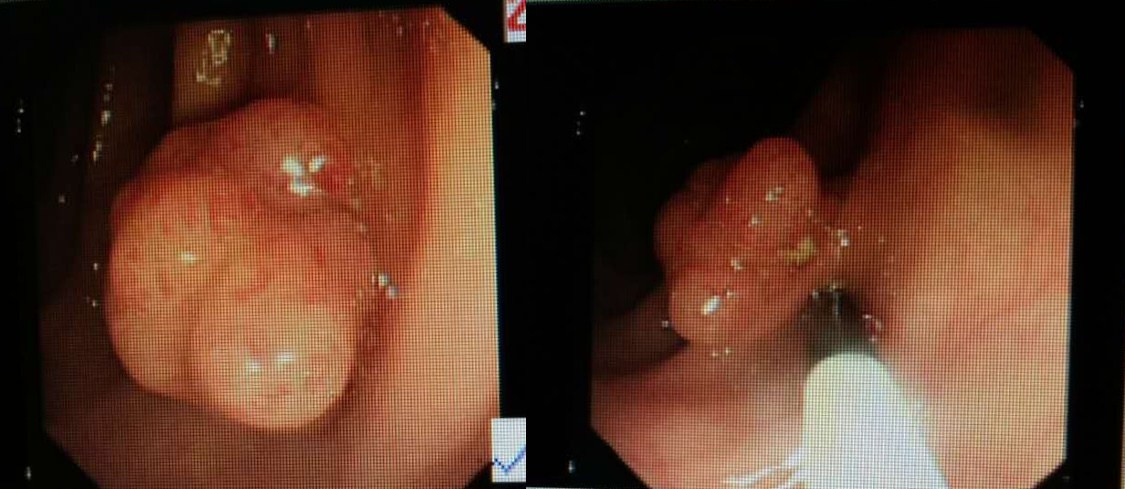

大肠息肉,你肚子里的定时炸弹!切除了也要复查!